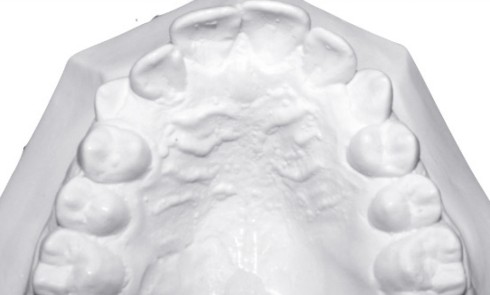

Article réservé à nos abonnés Traitement d’une Classe II subdivision gauche avec DDM dans un contexte de mésodivergence

Présentation du cas Kenny, âgé de 12 ans, sans antécédent orthodontique, consulte pour ses malpositions dentaires. Examen exobuccal (fig. 1a-c)...